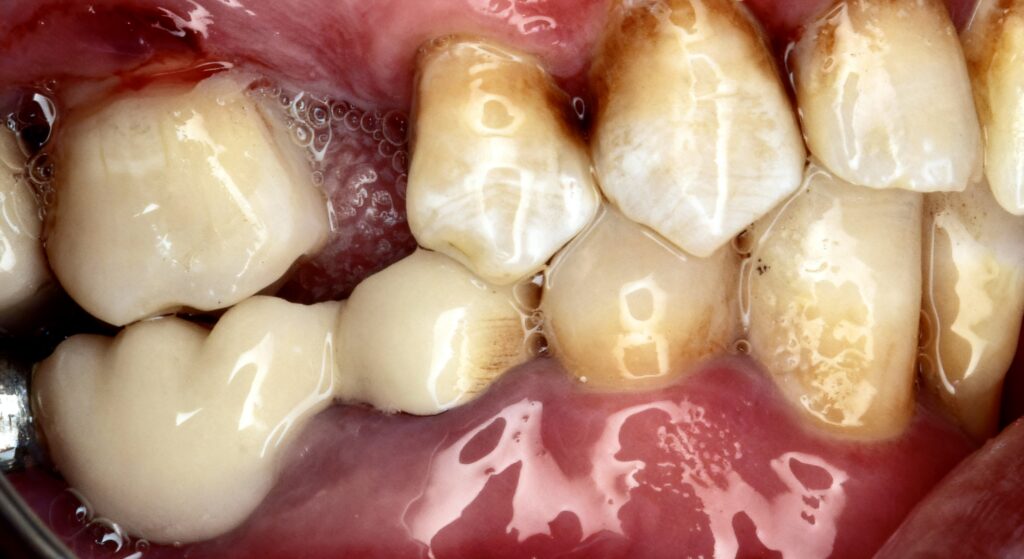

- Endodontically treated posterior tooth

- Moderate to extensive loss of coronal structure